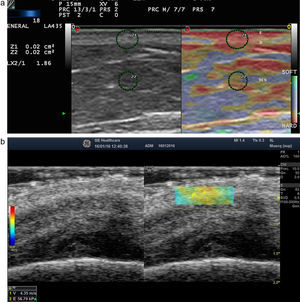

Elastografía de la piel normal y los anejosLa dureza de la piel sana varía en función del estrato cutáneo estudiado. La dermis es una estructura de rigidez superior al tejido celular subcutáneo16 (figs. 2a,b). En el tejido celular subcutáneo, los septos presentan mayor rigidez que los lobulillos grasos. Los vasos sanguíneos son estructuras poco rígidas, al igual que los nervios periféricos, en comparación con el tejido celular subcutáneo circundante16.

a) Elastografía de strain de la piel normal. Obsérvese el ratio de rigidez de dermis y la grasa SR=1,86 que indica que la dermis es más dura que el tejido celular subcutáneo.

E: epidermis; D: dermis; TCS: tejidocelular subcutáneo.

b) Elastografía SW de la dermis del cuero cabelludo. Obsérvese en la esquina inferior derecha los parámetros de velocidad y presión de la región de interés analizado (rectángulo verde-amarillento).

En la uña sana, la tabla ungueal es rígida en comparación con el lecho ungueal 17 (fig. 3).